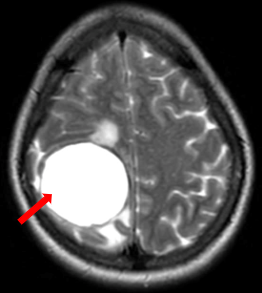

Sau 8 tháng điều trị, bệnh nhân không còn ghi nhận những cơn co giật, bệnh nhân không khó thở, không đau ngực. Trên phim chụp cộng hưởng từ não, kích thước khối u giảm đáng kể là một minh chứng cho sự đáp ứng tốt với thuốc của bệnh nhân. Phim chụp cắt lớp vi tính cũng ghi nhận kích thước khối u giảm hơn so với phim chụp cũ.

Hình 3. Hình ảnh phim chụp cộng hưởng từ não ngày 28 tháng 6 năm 2023 (mũi tên trắng) so với ngày 27 tháng 10 năm 2022 (mũi tên đỏ), kích thước khối u giảm so với phim chụp cũ.